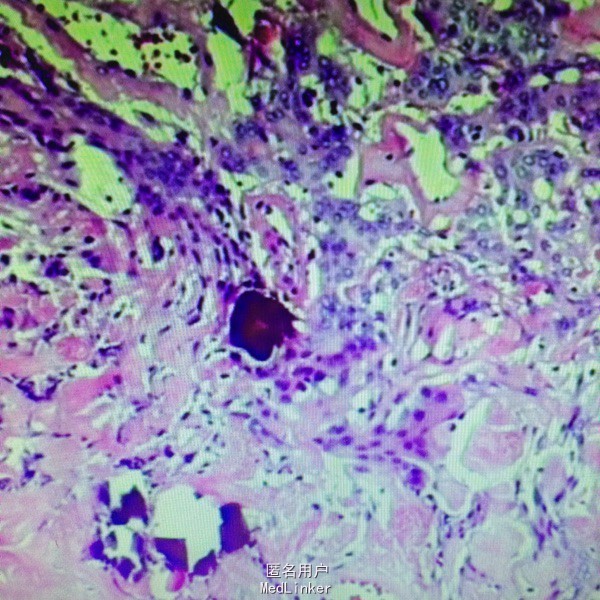

诊断:左侧额叶非典型脑膜瘤 处理:行左额占位切除术➕颅骨重建术,病理提示非典型脑膜瘤

随访:术后患者出现右侧中枢性面瘫……后缓解出院。 讨论:本患者属于非典型脑膜瘤,非典型性脑膜瘤是介于良性脑膜瘤和恶性脑膜瘤之间的中间型肿瘤,2000年世界卫生组织(WHO)的分类中将其定为Ⅱ级,属低度恶性肿瘤 ,可行手术切除治疗。